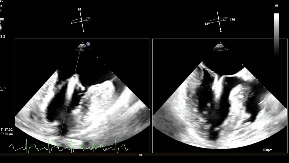

手术过程

患者麻醉后取平卧位,经食管超声(TEE)探头置入到位。股静脉穿刺点消毒铺巾后进行穿刺,并置入鞘管建立工作路径。置入超声引导专用导丝(Panna Wire)和房间隔穿刺针。Panna Wire梭形头端在超声下具有优异的可视性与指向性,将其置入穿刺针内,可实时指导穿刺针的位置。在TEE实时引导下,完成房间隔穿刺。因左心房容积偏小,操作空间受限,故穿刺点选择略靠后,但操作过程顺利,未损伤左心房后壁。

术中影像

房间隔穿刺

置入瓣膜夹

第一次关闭瓣膜夹

超声提示仍存在少量反流